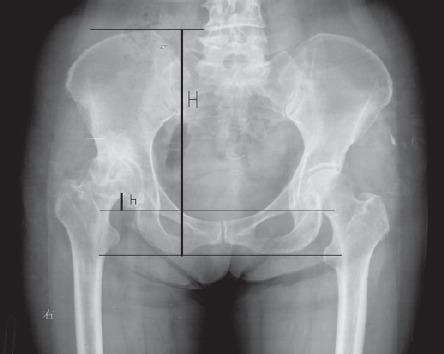

To investigate whether adult patients with unilateral developmental dysplasia of the hip (UDDH) have pelvic asymmetry and what correlation existing between them. Methods: A total of 100 adult patients with UDDH were enrolled in the retrospective observational study in Shanghai Jiaotong University Affiliated Sixth People's Hospital, Shanghai, China, between January 2012 and February 2014. The anteroposterior pelvic radiographs were reviewed and the pelvic heights and ischium heights were measured and compared between the affected and non-affected sides to find out the relationship between the pelvic morphology and hip dysplasia. Results: The pelvic heights demonstrated significant differences between the non-affected side and the affected side in patients with Crowe type II-IV UDDH (p less than 0.05), but not in patients with Crowe type I UDDH (p=0.09). There were significant differences in the bilateral ischium heights in patients with Crowe type III and IV UDDH (p less than 0.05), but not in patients with Crowe type I and II UDDH (p=0.78, p=0.055). In addition, the degree of hip dysplasia was positively associated with the degrees of asymmetry of pelvis (r=0.78, p less than 0.001) and ischium (r=0.72, p less than 0.001) in UDDH patients. Conclusion: The pelvic asymmetry exists in adult patients with UDDH. In addition, the degree of asymmetry has correlation with the degree of hip dysplasia. We recommend that it should be taken more cautions to use teardrops and ischial tuberosity as anatomy landmarks to balance leg-length discrepancy for unilateral DDH patients in preoperative planning and total hip arthroplasty.

探讨成年单侧发育性髋关节发育不良(UDDH)患者是否存在骨盆不对称及其之间的相关性。方法:2012年1月至2014年2月,在上海交通大学附属第六人民医院对100例成年UDDH患者进行回顾性观察研究。回顾骨盆前后位X线片,测量并比较患侧与非患侧的骨盆高度和坐骨高度,以了解骨盆形态与髋关节发育不良之间的关系。结果:Crowe II-IV型UDDH患者非患侧与患侧的骨盆高度存在显著差异(p<0.05),而Crowe I型UDDH患者无显著差异(p=0.09)。Crowe III型和IV型UDDH患者双侧坐骨高度存在显著差异(p<0.05),而Crowe I型和II型UDDH患者无显著差异(p=0.78,p=0.055)。此外,UDDH患者髋关节发育不良程度与骨盆不对称程度(r=0.78,p<0.001)和坐骨不对称程度(r=0.72,p<0.001)呈正相关。结论:成年UDDH患者存在骨盆不对称。此外,不对称程度与髋关节发育不良程度相关。我们建议,在术前规划和全髋关节置换术中,对于单侧DDH患者,以泪滴和坐骨结节作为解剖标志来平衡肢体长度差异时应更加谨慎。